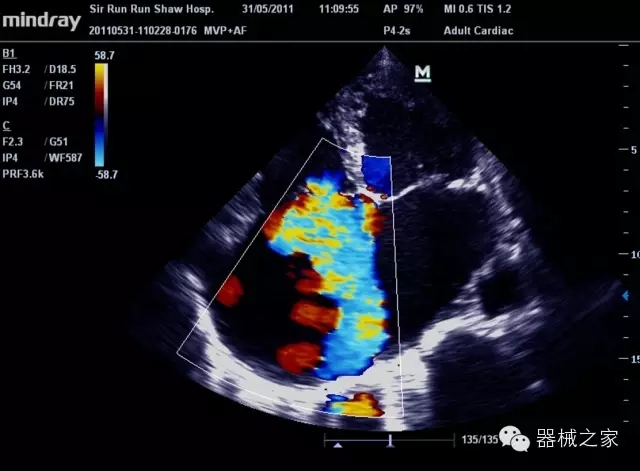

臨床圖片賞析

產(chǎn)品特點

·裝載有采用Multi-Core多核處理的非嵌入式平臺,成像效率大大提高,并且能夠給用戶帶來高速、多任務(wù)并行信號處理體驗;

·優(yōu)秀的圖像效果、強大的功能體驗、豐富的探頭選擇、合理的便攜式設(shè)計,全中文顯示及病人管理界面,使得M7在任何場合、任何時候都能快速響應(yīng)更好的心血管、腹部、婦產(chǎn)、小器官等常規(guī)超聲檢查以及肌骨、神經(jīng)、顱腦、術(shù)中等新興領(lǐng)域的使用需求;

8倍波束并行處理系統(tǒng)

·在便攜式緊湊平臺上采用更多倍波束并行接收信號處理模式,無論二維還是彩色血流圖像狀態(tài)下,擁有更靈敏的回波頻移捕獲能力,大大提高時間分辨率,尤其使得心血管表現(xiàn)更為突出;